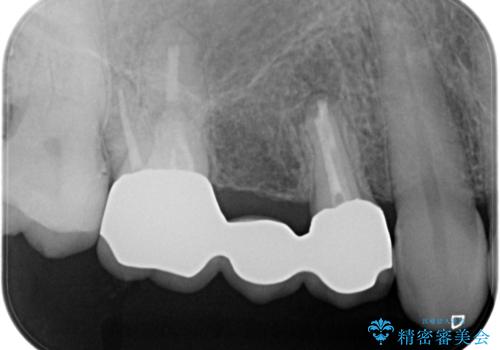

歯肉を押すと痛みがあり、レントゲンの画像でも病変があることがわかります。

前医にてラバーダムを用いた根管治療が完了していたため、歯根の先端を切除する治療を行いました。